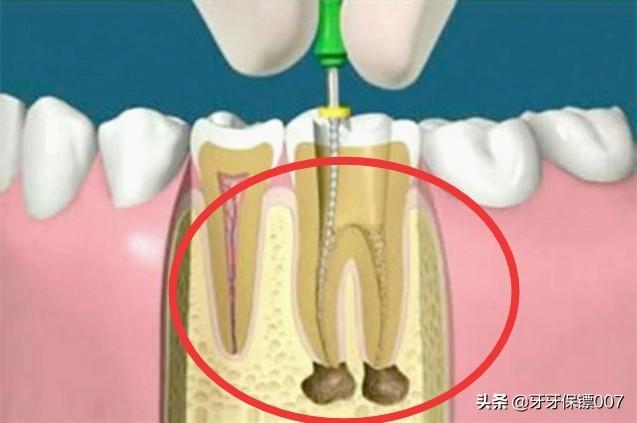

Par exemple, le plus courant est le traitement du canal radiculaire, en cas de pulpite ou de nécrose pulpaire, qui consiste d'abord à retirer la pulpe malade, ce qui permet de résoudre le problème des maux de dents et, ensuite, de faciliter la restauration dentaire en portant des couronnes en porcelaine.

J'ai décidé de faire un traitement de canal seulement après avoir confirmé avec le médecin encore et encore. Au début, j'ai aussi baidu quelques informations, beaucoup de gens disent ne pas avoir un traitement de canal, un bon médecin ne proposera pas d'aller au traitement de canal ? Parce qu'après tout, la dent après le canal radiculaire ne peut pas absorber les nutriments à travers l'alvéole, de sorte que la dent ne fera que s'aggraver de plus en plus, et finalement jusqu'à la fin de l'irréparable. Le traitement de canal implique également le port d'une couronne, sans parler du prix de la couronne, de son élégance, etc. ...... Je n'aime donc pas beaucoup le médecin qui m'a proposé de me faire un traitement de canal.

Si la pulpe n'est pas blessée et ne provoque pas de pulpite, il est généralement possible d'obturer directement la dent ! Le prix est également relativement bon marché, il y a généralement plusieurs types de matériaux à choisir, plusieurs centaines de dollars ! Si la pulpe de la dent est suffisamment profonde pour provoquer une pulpite, vous devrez subir un traitement de canal ! Qu'est-ce qu'un traitement de canal ? Cela signifie simplement que le nerf de la dent est tué et qu'une fois le traitement de canal effectué, la dent ne fera plus jamais mal !

Les tarifs des traitements de canal varient d'un endroit à l'autre, certains facturant en fonction du nombre de canaux dans votre dent, et d'autres en fonction du type de dent que vous avez ! En général, les grandes dents et les incisives sont plus chères ! Un traitement de canal coûte entre 1 500 et 3 000 euros pour une seule dent, et comme il faut éliminer la carie à l'intérieur de la dent, il faut aussi faire des plombages.